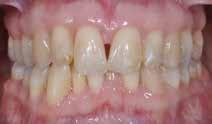

Den kliniske undersøgelse viser harmoniske ekstraorale sagittale forhold med skeletalt dybt bid (Fig. 1A, D). Hendes smil er alderssvarende med en eksponering på 8/10 af overkæbeincisiverne, mens smilets bredde er smalt med synlige mørke laterale rum (Fig. 1D). Underkæbeincisiverne er synlige under tale. Der ses neutrale okklusale forhold ved hjørnetænderne og neutrale pladsforhold i overkæben, men udtalt trangstilling i underkæben især lokaliseret i regio 1-1 (Fig. 1C).

Sliddet klassificeres som grad 2 (moderat tandslid) på de centrale incisiver i overkæbe og underkæbe. Det kan anses som patologisk, da det er atypisk for patientens alder, giver anledning til smerte/ubehag, og giver patienten et æstetisk problem. Der ses infraktioner af overkæbeincisiverne. Der ses endvidere en udtalt Spee-kurve i underkæben og ingen interincisal afstøtning på 2-2 med let ganepåbidning.

Patienttilfælde 1 (Fig. 1) er en 37-årig kvinde, henvist efter succesfuld behandling af stadie 3-parodontitis. Der er nu sundt

Før behandling

parodontium, ingen pocher over 4 mm, og både blødnings- og plakindeks er under 10 %. Patienten er motiveret for ortodontisk behandling, da hendes tænder er vandret over tid, delvist som følge af reduceret parodontium.

Der ses anterior trangstilling i begge kæber og overerupterede 1+1 og 2,1-1,2, hvilket resulterer i dybt bid med 2- tæt på ganepåbidning. Der er normale sidetandsrelationer, men der ses 5 mm horisontalt overbid (HOB) og 7 mm vertikalt

overbid (VOB). Papillen mellem 1+1 er betydeligt reduceret pga. fæstetab, og de mesialt kippede 1+1 har resulteret i en ”dark triangle”. Den facioorale funktion er for nuværende i.a. Panoramarøntgen (Fig. 1, I) viser marginalt knogletab i begge kæber og fravær af 8,7+7,8 og 8,7-8.